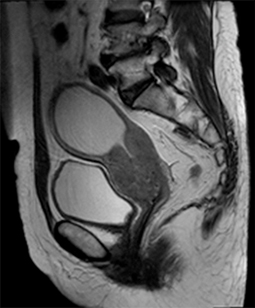

[사진 출처 : 국가암정보센터 http://www.cancer.go.kr]